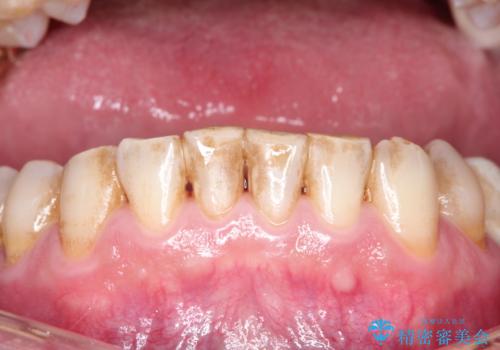

ステインによる歯の着色

- 日頃の積み重なった茶渋・着色をエアフローにてクリーニングしました。

歯についている茶しぶやタバコによるヤニは着色を落とす専用器具を使用しないと綺麗に取り除くことはできません。

歯の表面に着色が付いて黄ばんで見えることがあるため、PMTCを行うとご自身の歯本来の色味にすることができます。